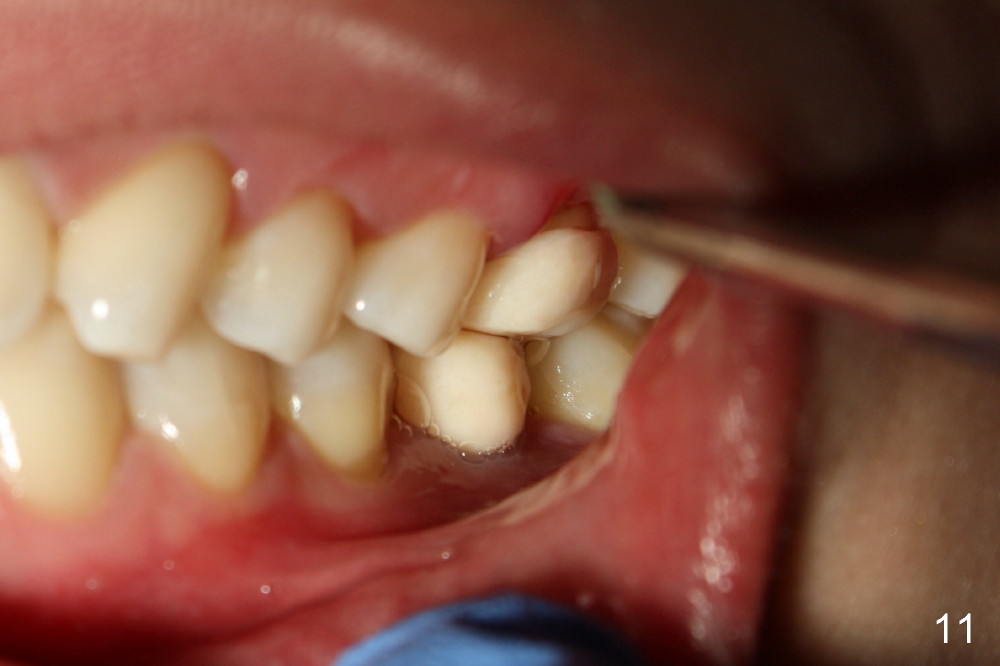

一旦下颌牙冠决定后,适当调整上牙牙冠制备,制做临时牙冠,咬合仿佛改善不少(图十一,与图七比较),上颌临时牙冠低多了(图十二,与图六相比)。在气急败坏下,突然领悟到一个真理:缺失一个磨牙,邻近咬合变化是巨大而且复杂的,例如下颌第二磨牙,不仅往近中倾斜移位,而且往舌侧倾倒(图一,二),发生三维变化,图十二还显示上颌前臼齿也不整齐,大概第二磨牙也有不同程度位置变化。